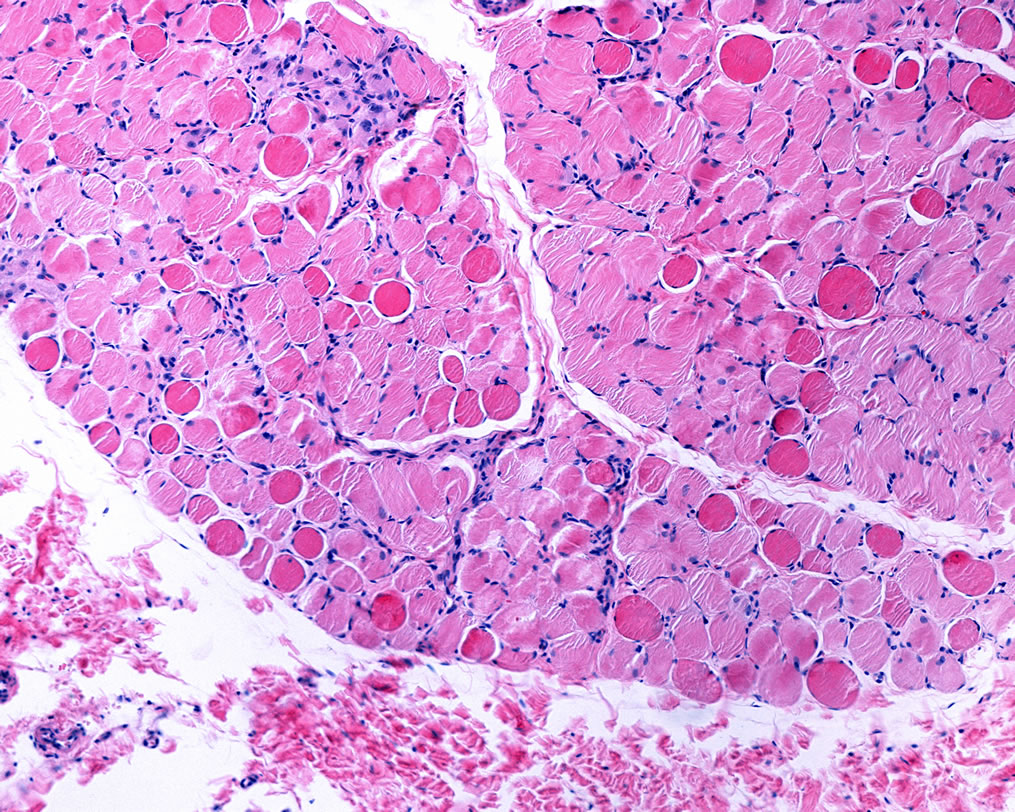

GLUT4 X-Linked-Myotubular-Myopathy

OUR SCIENCE X-Linked Myotubular Myopathy

X-linked myotubular myopathy (MTM) is a neuromuscular disorder caused by mutations in the

myotubularin (MTM1) gene. It is a rare condition (estimated at 1:50,000 male births) associated with substantial morbidities and early mortality.